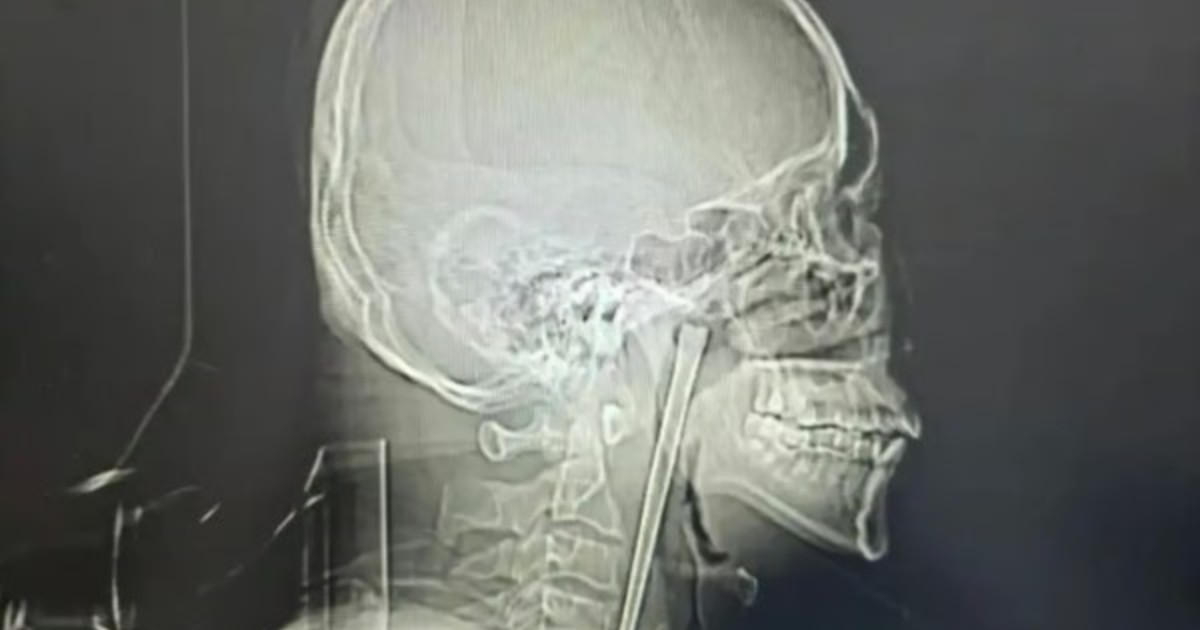

Soledad Davico, madre de Claribel: "El director del hospital me llamó para lavarse las manos" Febrero 01, 2024 1329